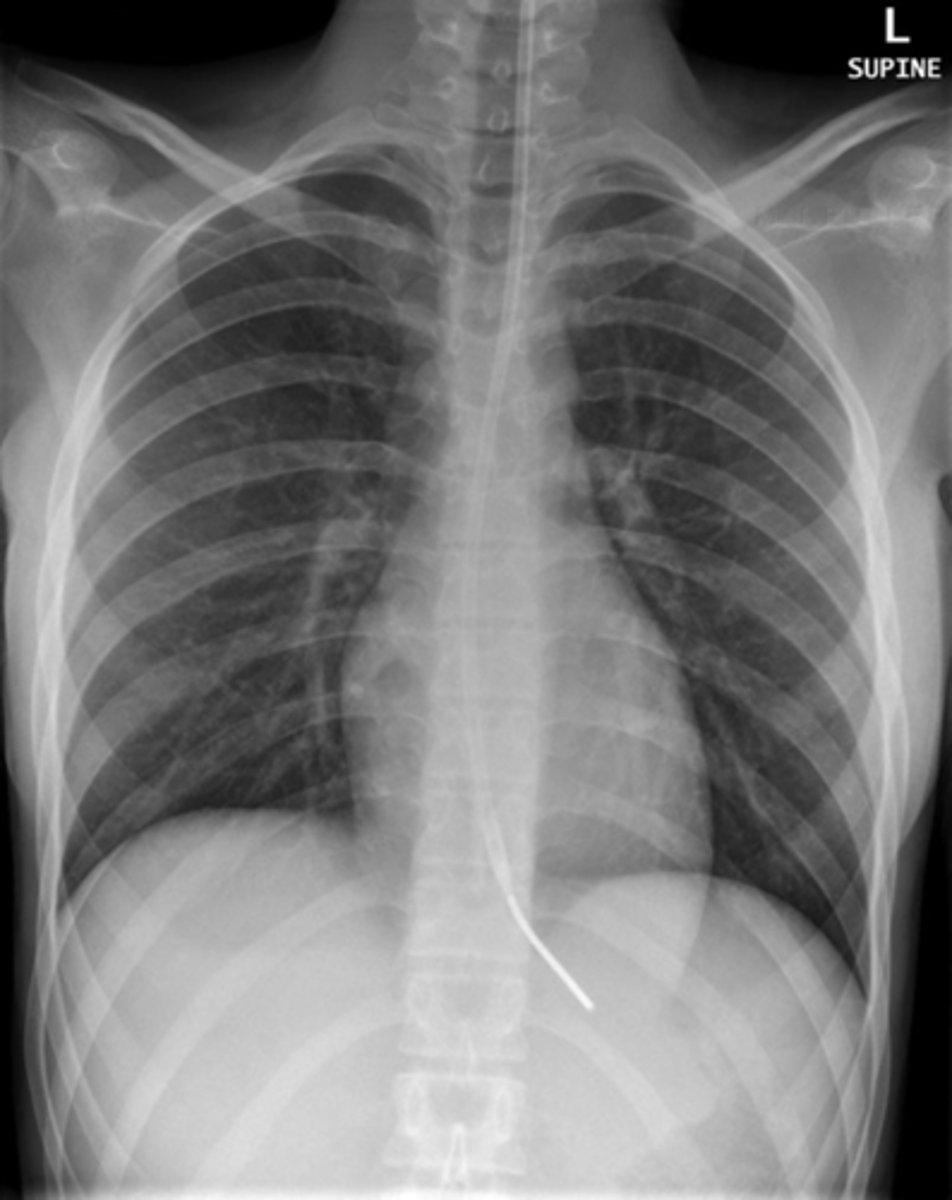

Atelectasis (collapsed area looks white and a tracheal shift)

Interpretation?